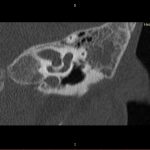

- Diagnosticul traumatismelor de bază de craniu

- Diagnosticul fracturilor:

- Complexe cranio-sinusale

- Complexe cranio-etmoidale

- Complexe cranio-orbitare

- Complexe cranio-faciale